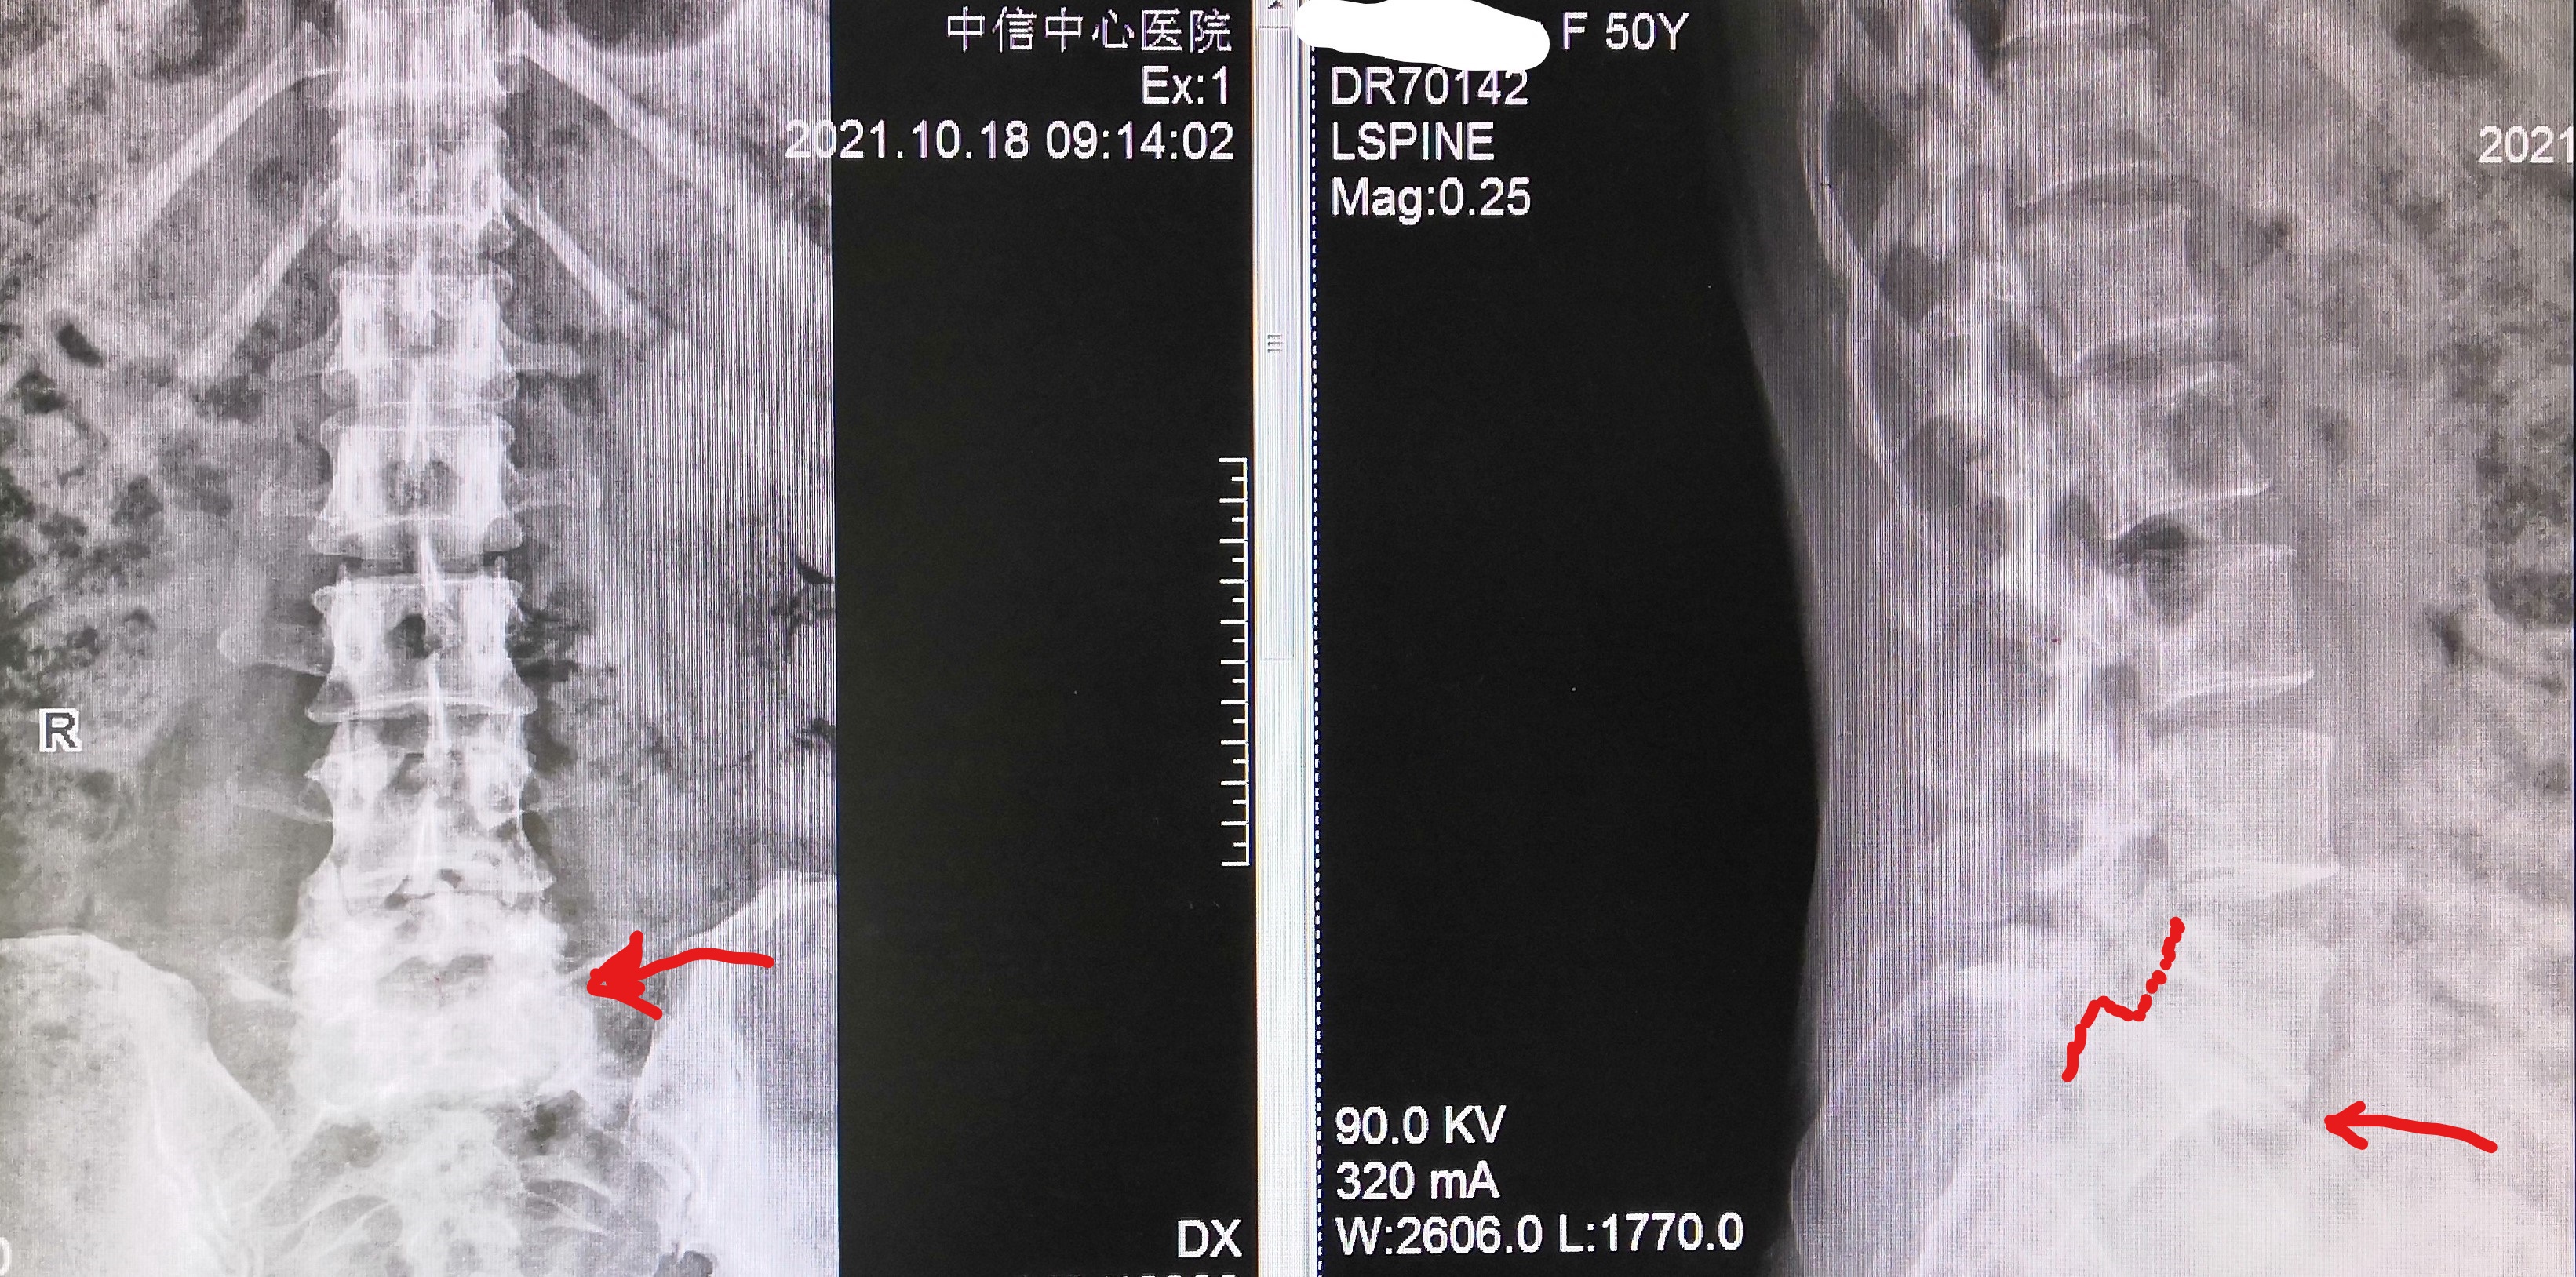

腰椎正侧位X光片显示:腰5相对骶1 有二度滑脱,形成台阶

椎间隙狭窄,腰5骶1椎间隙前缘骨性增生明显(红色曲线及箭头指示)